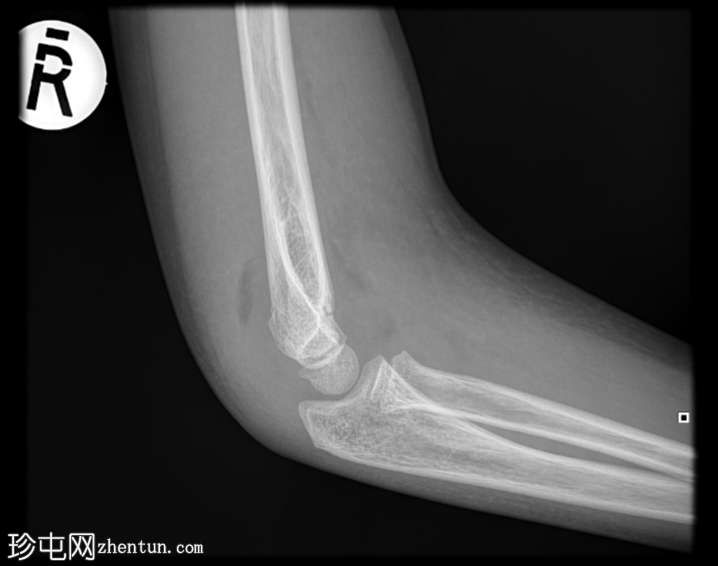

X线片

侧位片

右侧肱骨远端Gartland I型髁上骨折。无急性脱位。肘关节前后脂肪垫突出,提示肘关节积液。桡骨近端和尺骨近端正常。